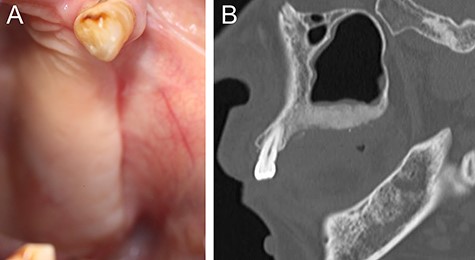

(A) Intraoral photograph showing gingival fistulas in #25 and #26 extraction sites (arrows). (B) Sagittal section of CT image showing separated sequestrums in the left maxilla (arrow) and bone resorption in the periapical area of #24 (arrowhead).

At 1 year after the extractions, a purulent discharge and exposed bone with gingival fistulas were observed in the extraction sites (Fig. 2A). CT images revealed separated sequestrums in the left maxilla and bone resorption in the periapical area of the left maxillary first premolar (FDI #24) (Fig. 2B). With the permission of the patient’s attending physicians, the alendronate was withdrawn. After exposed bone had been observed for 8 weeks, the patient was clinically diagnosed with Stage 2 BRONJ accompanying FD of the left maxillary bone. Under general anesthesia, we first performed extraction of #24 and sequestrectomy. We then performed a partial resection of the FD because necrotic-like bone fragments were collected by curettage of the marginal bone (Fig. 3). Finally, the surgical wound was completely closed by sutures. The histopathological diagnosis was chronic osteomyelitis with FD (Fig. 4). At 2.5 years after the operation, the healing is uneventful although residual FD bone exists (Fig. 5). Although local conditions permit the resumption of alendronate, it remains discontinued at the attending physicians’ discretion.

(A) Six-month postoperative intraoral photograph showing complete healing of a surgical wound. (B) Sagittal section of CT image showing residual but not recurrently infected FD bone in the left maxilla after surgical resection.